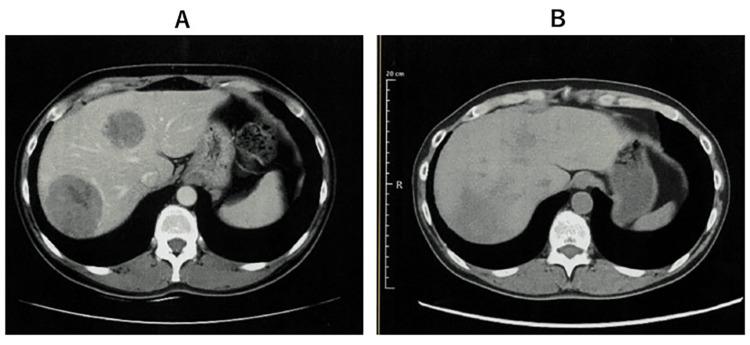

Among cervical cancers, small cell undifferentiated carcinoma is rare. Because of its rapid progression, the prognosis is extremely poor. During the course of cisplatin-based chemotherapy for stage Ⅳ small cell undifferentiated carcinoma of the cervix, the patient developed drug resistance, and standard treatment was no longer feasible. Therefore, immunoradiotherapy was administered to activate anticancer immunity. Surprisingly, the cancer drug sensitivity was restored, and cisplatin was again successful, and the cancer disappeared. In addition, the activation of cancer-specific immunity maintained the disappearance of the cancer. It should be noted that immunoradiotherapy not only increases anti-cancer immunity but may also contribute to overcoming cancer drug resistance.

在宫颈癌中,小细胞未分化癌较为罕见。由于其进展迅速,预后极差。在对一名Ⅳ期宫颈小细胞未分化癌患者进行以顺铂为基础的化疗过程中,患者出现了耐药性,标准治疗不再可行。因此,给予免疫放疗以激活抗癌免疫。令人惊讶的是,癌症药物敏感性得以恢复,顺铂再次取得成功,癌症消失。此外,癌症特异性免疫的激活维持了癌症的消失。应当注意的是,免疫放疗不仅能增强抗癌免疫,还可能有助于克服癌症耐药性。